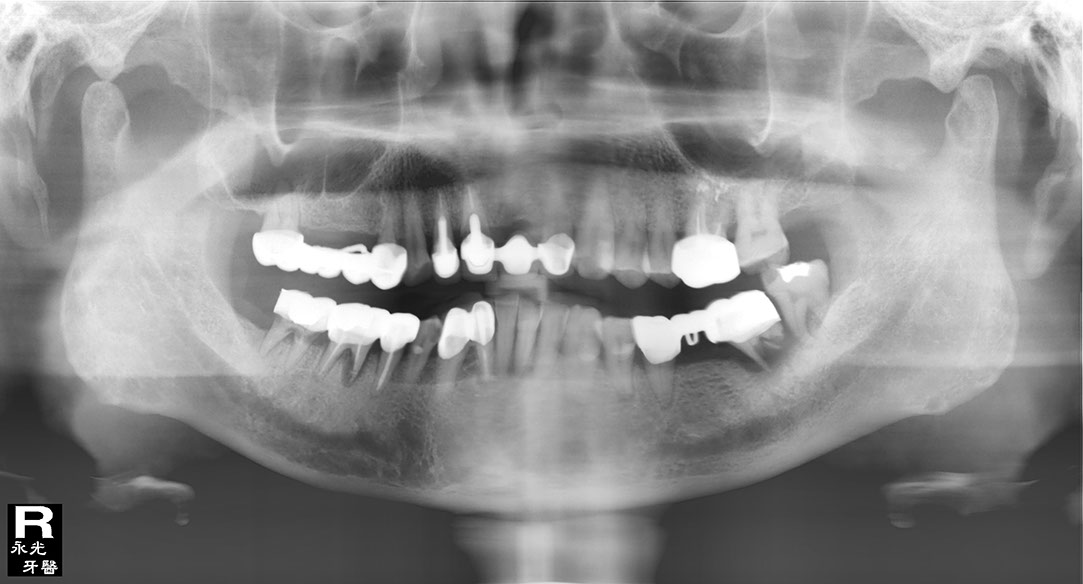

Implant 116d1.jpg

光牙醫